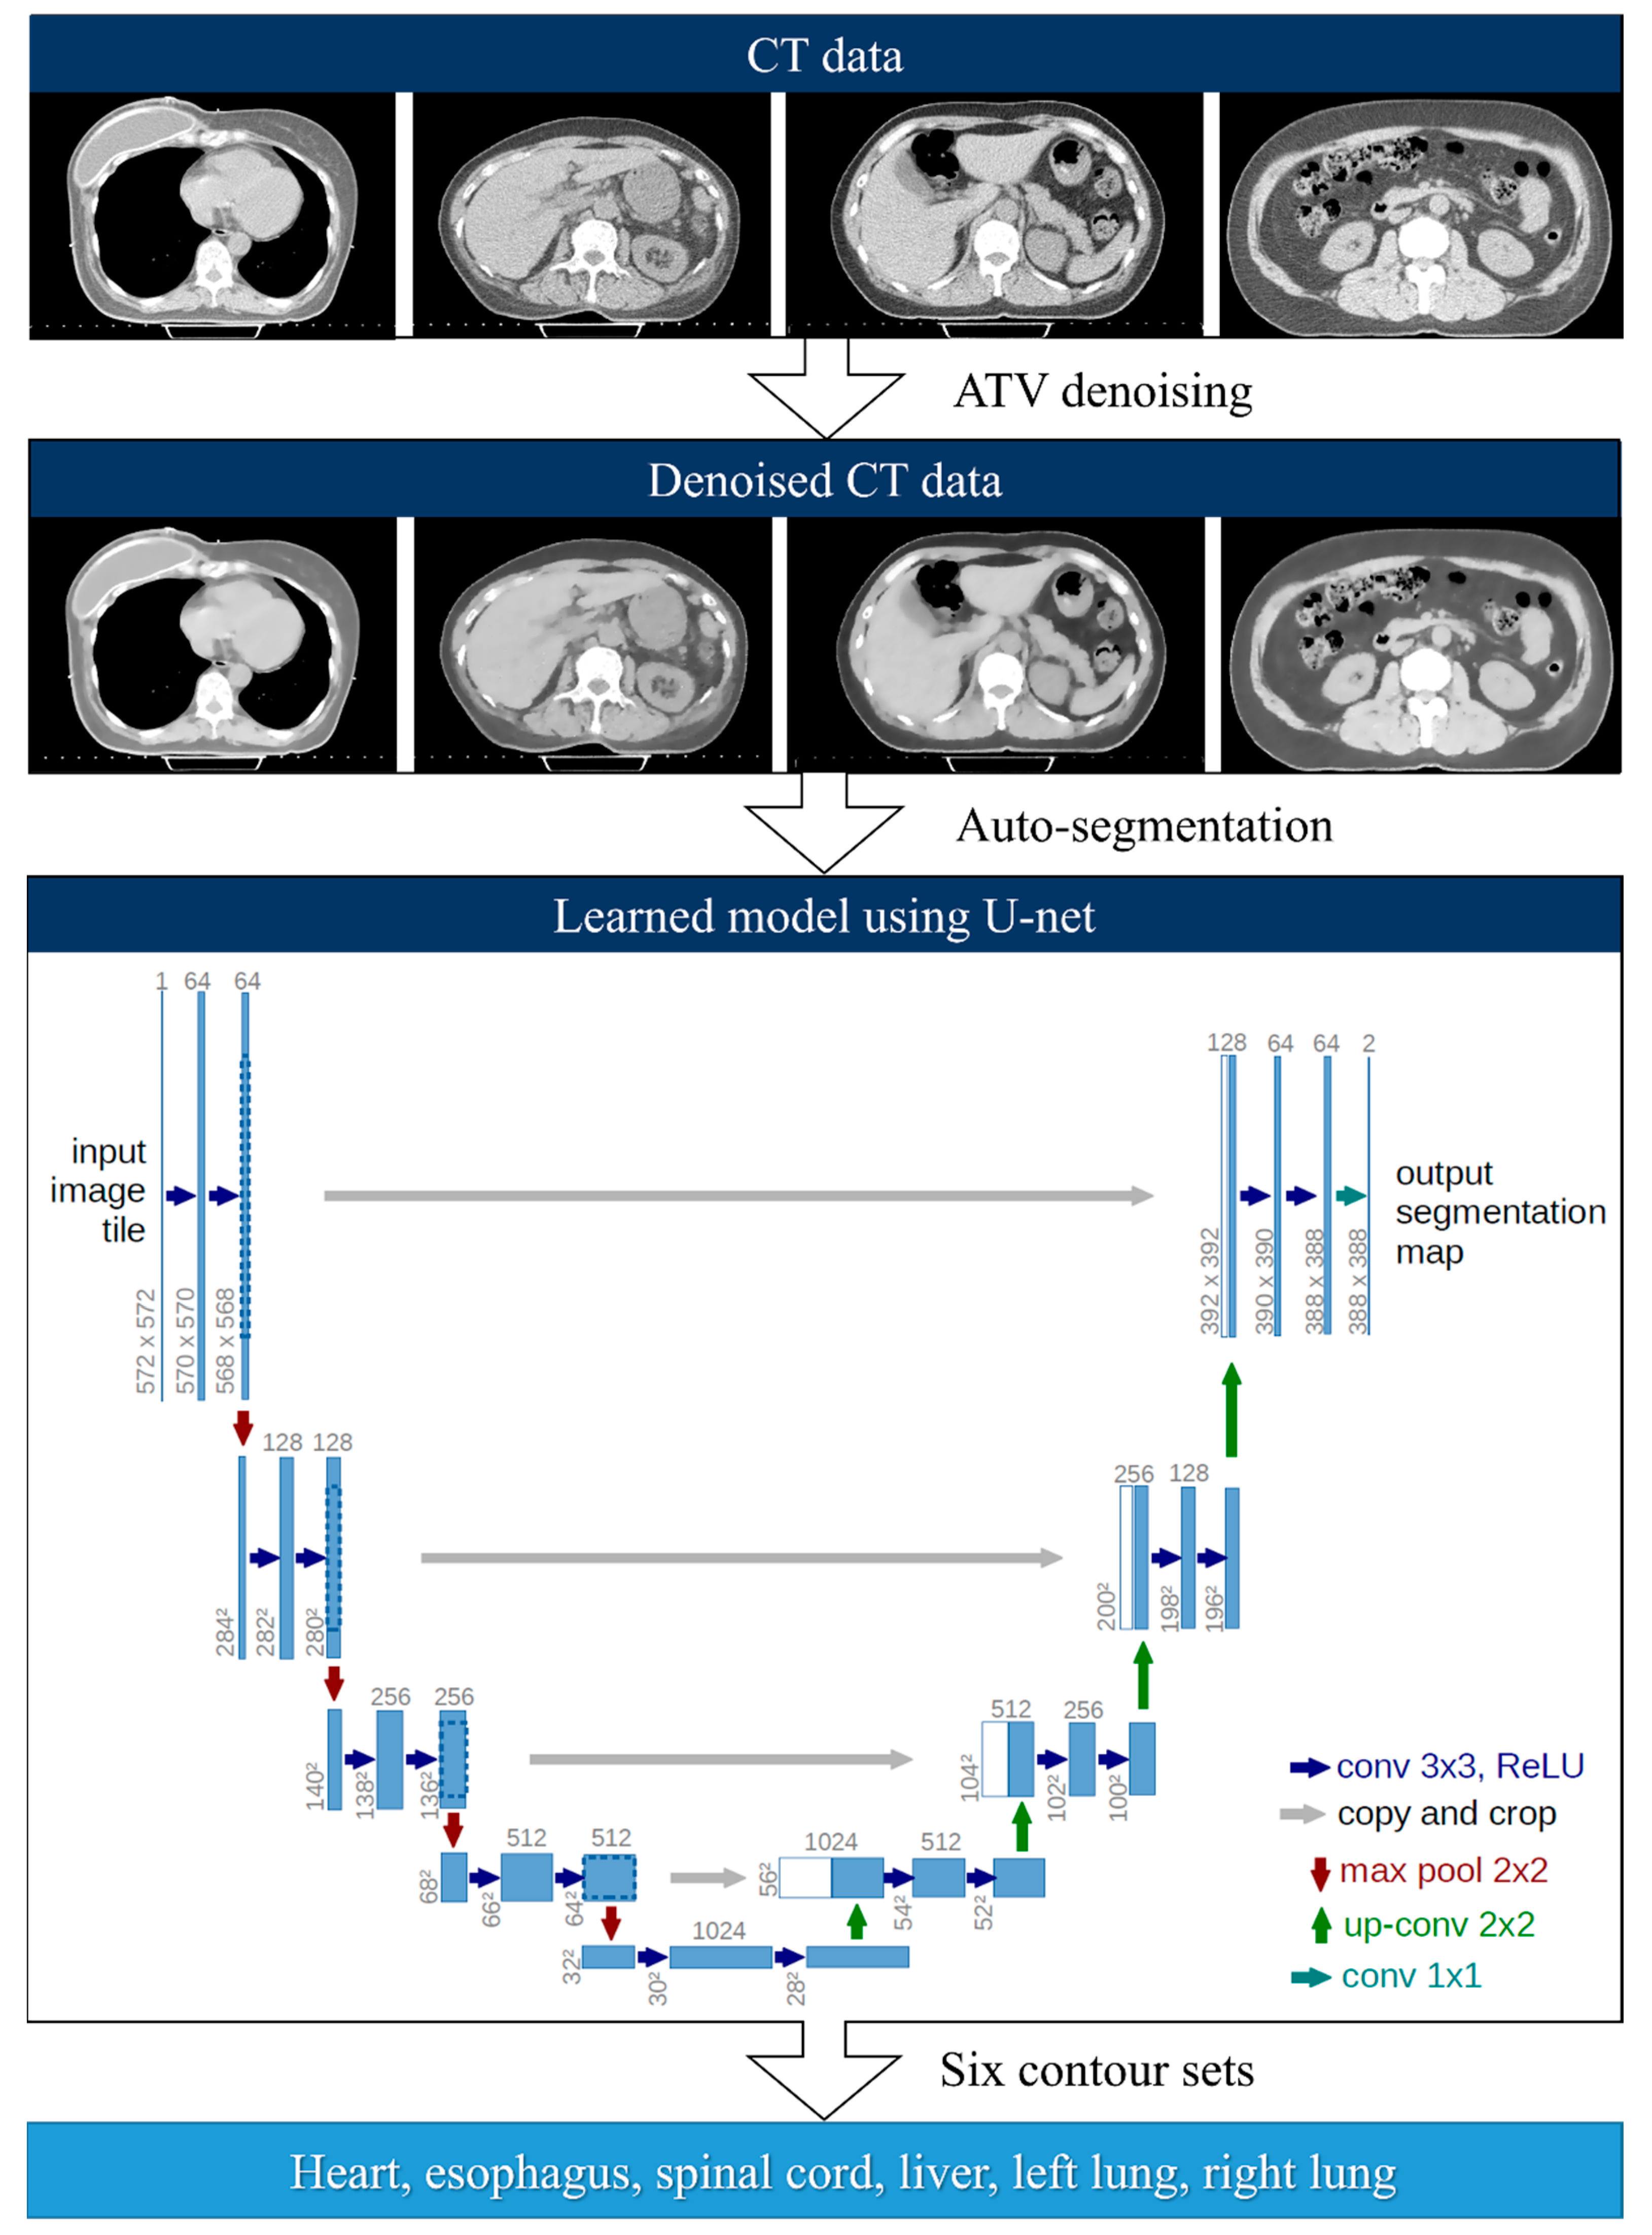

2.2. Deep-Learning-Based Auto-Segmentation

2.3. Anisotropic Total Variation Denoiser-Based Auto-Segmentation